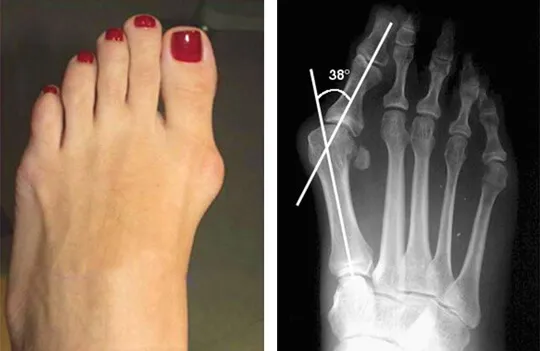

Leczenie operacyjne: kiedy jest koniecznością i na czym polega?

Wiem, że myśl o operacji może budzić obawy, ale w zaawansowanych przypadkach haluksów, gdy ból jest nie do zniesienia, deformacja znacząco utrudnia chodzenie, a wszystkie inne metody leczenia zachowawczego okazały się nieskuteczne, leczenie operacyjne staje się koniecznością. Celem operacji jest korekcja deformacji, przywrócenie prawidłowej anatomii stopy i, co najważniejsze, trwałe zmniejszenie lub całkowite wyeliminowanie bólu. Istnieje wiele technik operacyjnych, a wybór tej odpowiedniej zależy od stopnia zaawansowania haluksa i indywidualnych potrzeb pacjenta. Decyzja o operacji jest zawsze podejmowana wspólnie z pacjentem, po dokładnej analizie wszystkich za i przeciw.